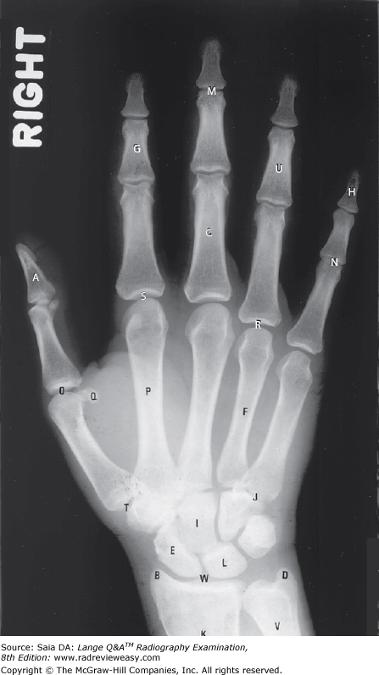

With which of the following does the trapezium articulate?

A Fifth metacarpal

B First metacarpal

C Distal radius

D Distal ulna

-The first metacarpal, on the lateral side of the hand, articulates with the most lateral carpal of the distal carpal row, the greater multangular/trapezium. This articulation forms a rather unique and very versatile saddle joint named for the shape of its articulating surfaces.